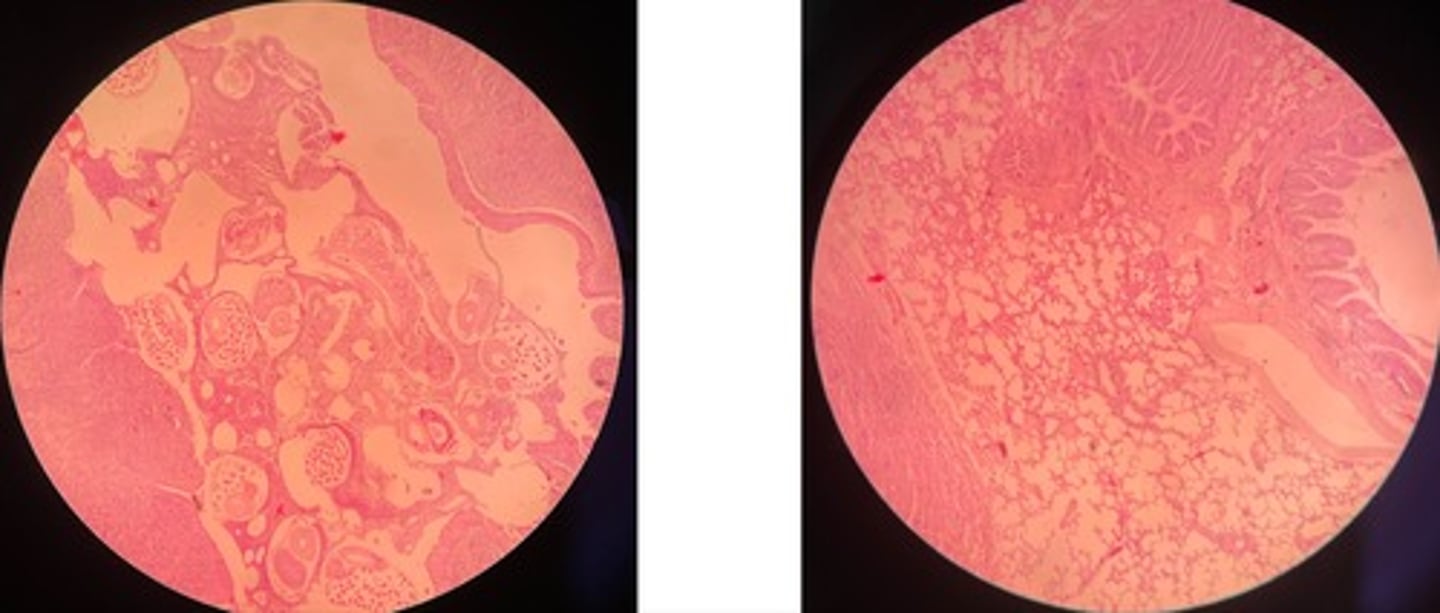

Catarrhal Bronchopneumonia

· thick bronchide walls

· catarral exudate in alveoli lumen (RBCs, leukocytes + mucous)

· congested vessels

· edema separates good + bad

Fibrinous Bronchopneumonia => mosaic appearance

· Acute = capillaries congested + alveoli filled w/light pink fluid

· Red = alveoli filled w/ exudate = fibrin + RBCs

· Grey = lots of neutrophils in lumen

· Resolution = fibrin in strands due to neutrophils enz release

Parasitic granuloma (of liver)

- dead parasites in centre surrounded by multinucleated giant cells

- regressive lesions of adjacent hepatocytes

Hepatic echinococcus

- cystic structure lined with chitin mem

- may have protoscolices (parasite larvae)

- liver parenchyma => atrophy, fatty degen, necrosis, haemorrhage

- infiltrate cells: macrophages, epitheliod cells and giant cells